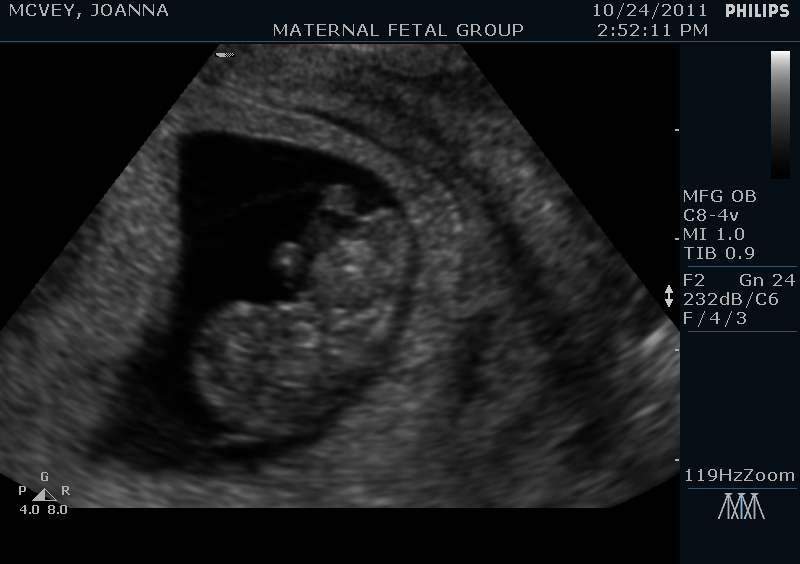

Well, I’ve made it past the half-way point in my pregnancy. Today I am 20 weeks and 5 days pregnant. This past Monday we had our anatomy scan ultrasound, and Baby McVey looked PERFECT! And in case you didn’t already know from reading my facebook page, Baby McVey is a BOY!!! Steve and I hadContinue reading “The Pregnancy Chronicles: 20 weeks (Half Baked!)”